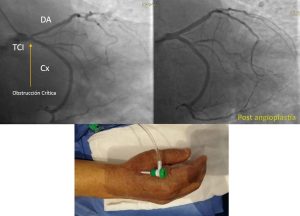

CASO CLINICO DE ANGIOPLASTÍA AL TRONCO CORONARIO IZQUIERDO (ARTERIA PRINCIPAL DEL CORAZÓN)

Ver Más »